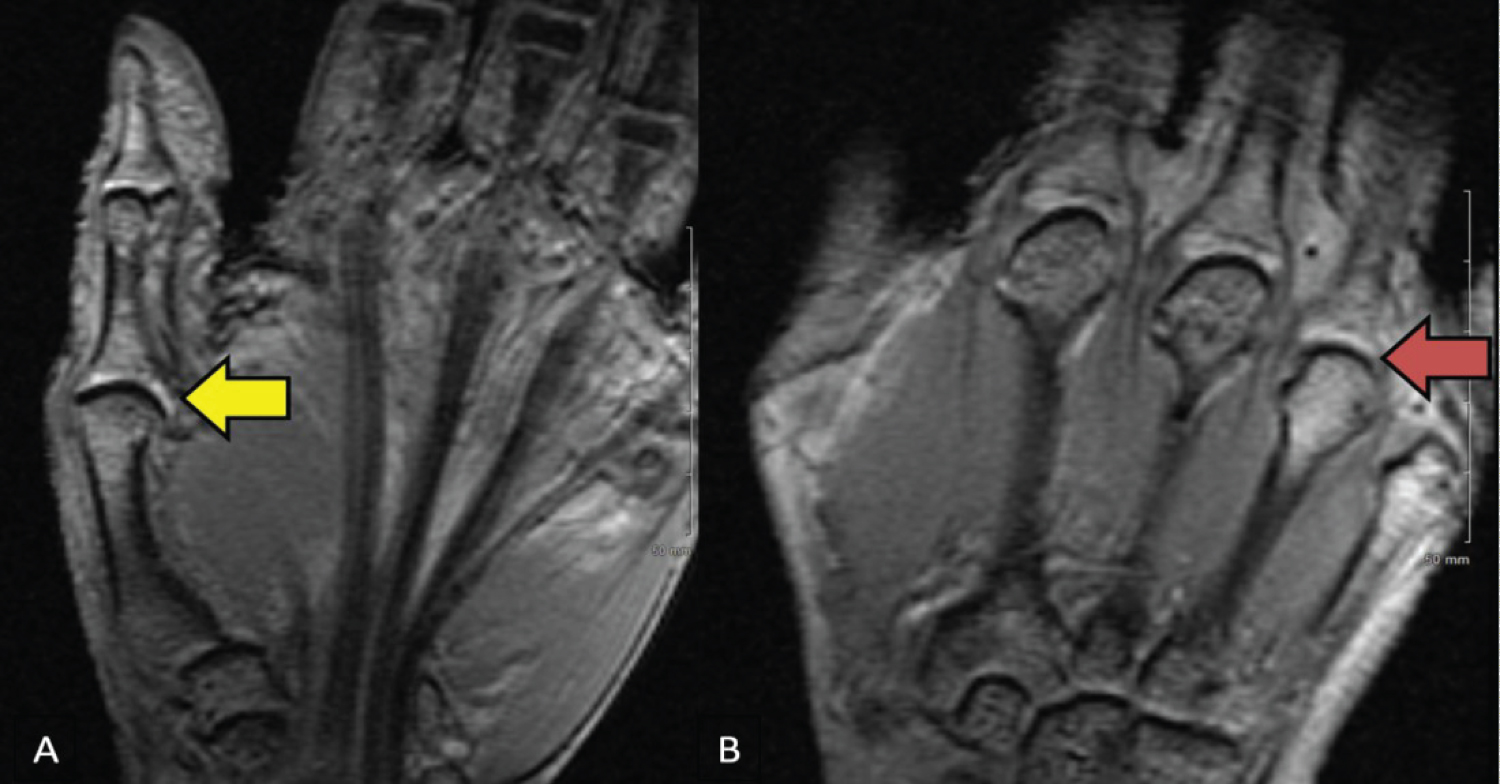

A 64-year-old female with unremarkable past medical history presented in our office with multiple swelling involving both dorsal hands over the last 2 months. The patient noticed having 5-10 minutes of morning stiffness, tenderness, and swelling in both hands, with decreased range of motion with minimal improvement with ibuprofen 800 mg daily. The patient denied acute injury, recent weight loss, Raynaud's phenomena, eye pain, oral ulcers, gastrointestinal complaints, or rash. On physical exam, a bony hypertrophic enlargement was noticed in the right 2nd finger distal interphalangeal (IP) joint and mild swelling in right 3rd, 4th, 5th metacarpophalangeal (MCP) joints with limited extension consistent with synovitis. Laboratory shown as noticed in Table 1. Subsequently, the next two days patient experienced the inability to extend her right 4th and 5th MCP joints and left 5th MCP joints consistent with tendon rupture (Figure 1). Due to the polyarticular distribution and multiple tendon ruptures, the patient was started on methotrexate 5 mg once weekly for possible seronegative rheumatoid arthritis (RA). Arthrocentesis was not possible due to the size of the joint and ongoing tendon ruptures. The patient was referred to orthopedics. Magnetic resonance imaging (MRI) of both hands showed hyperintense structures in the carpometacarpal (CMC) joint and 4th MCP joints (Figure 2). The patient underwent right-hand tenosynovectomy and tendon debridement of partial tears of the long finger extensors. The pathology report showed synovial hyperplasia, chronic lymphocyte-predominant perivascular inflammation, and positively birefringent crystals on polarization suggestive of calcium pyrophosphate dihydrate crystals (CPPD). The patient underwent additional surgery to repair the rest of the tendon (Figure 3). The patient started on colchicine 0.5 mg twice a day with subsequent symptom improvement. Laboratory for hemochromatosis and Wilson's disease were negative.

Figure 2: MRI of the left hand: (A) Yellow arrow pointed a T2 hyperintense structure along the medial aspect of the first CMC articulation, which measure approximately 11 × 3 × 3 mm. This may represent a small ganglion. Mild edema is demonstrated along the volar aspect of the base of the first metacarpal, likely related to adjacent degenerative etiology; (B) Red arrow pointed T2 hyperintense structure along the medial aspect of the fourth MCP articulation, which measure approximately 8 × 3 × 3 mm. View Figure 2